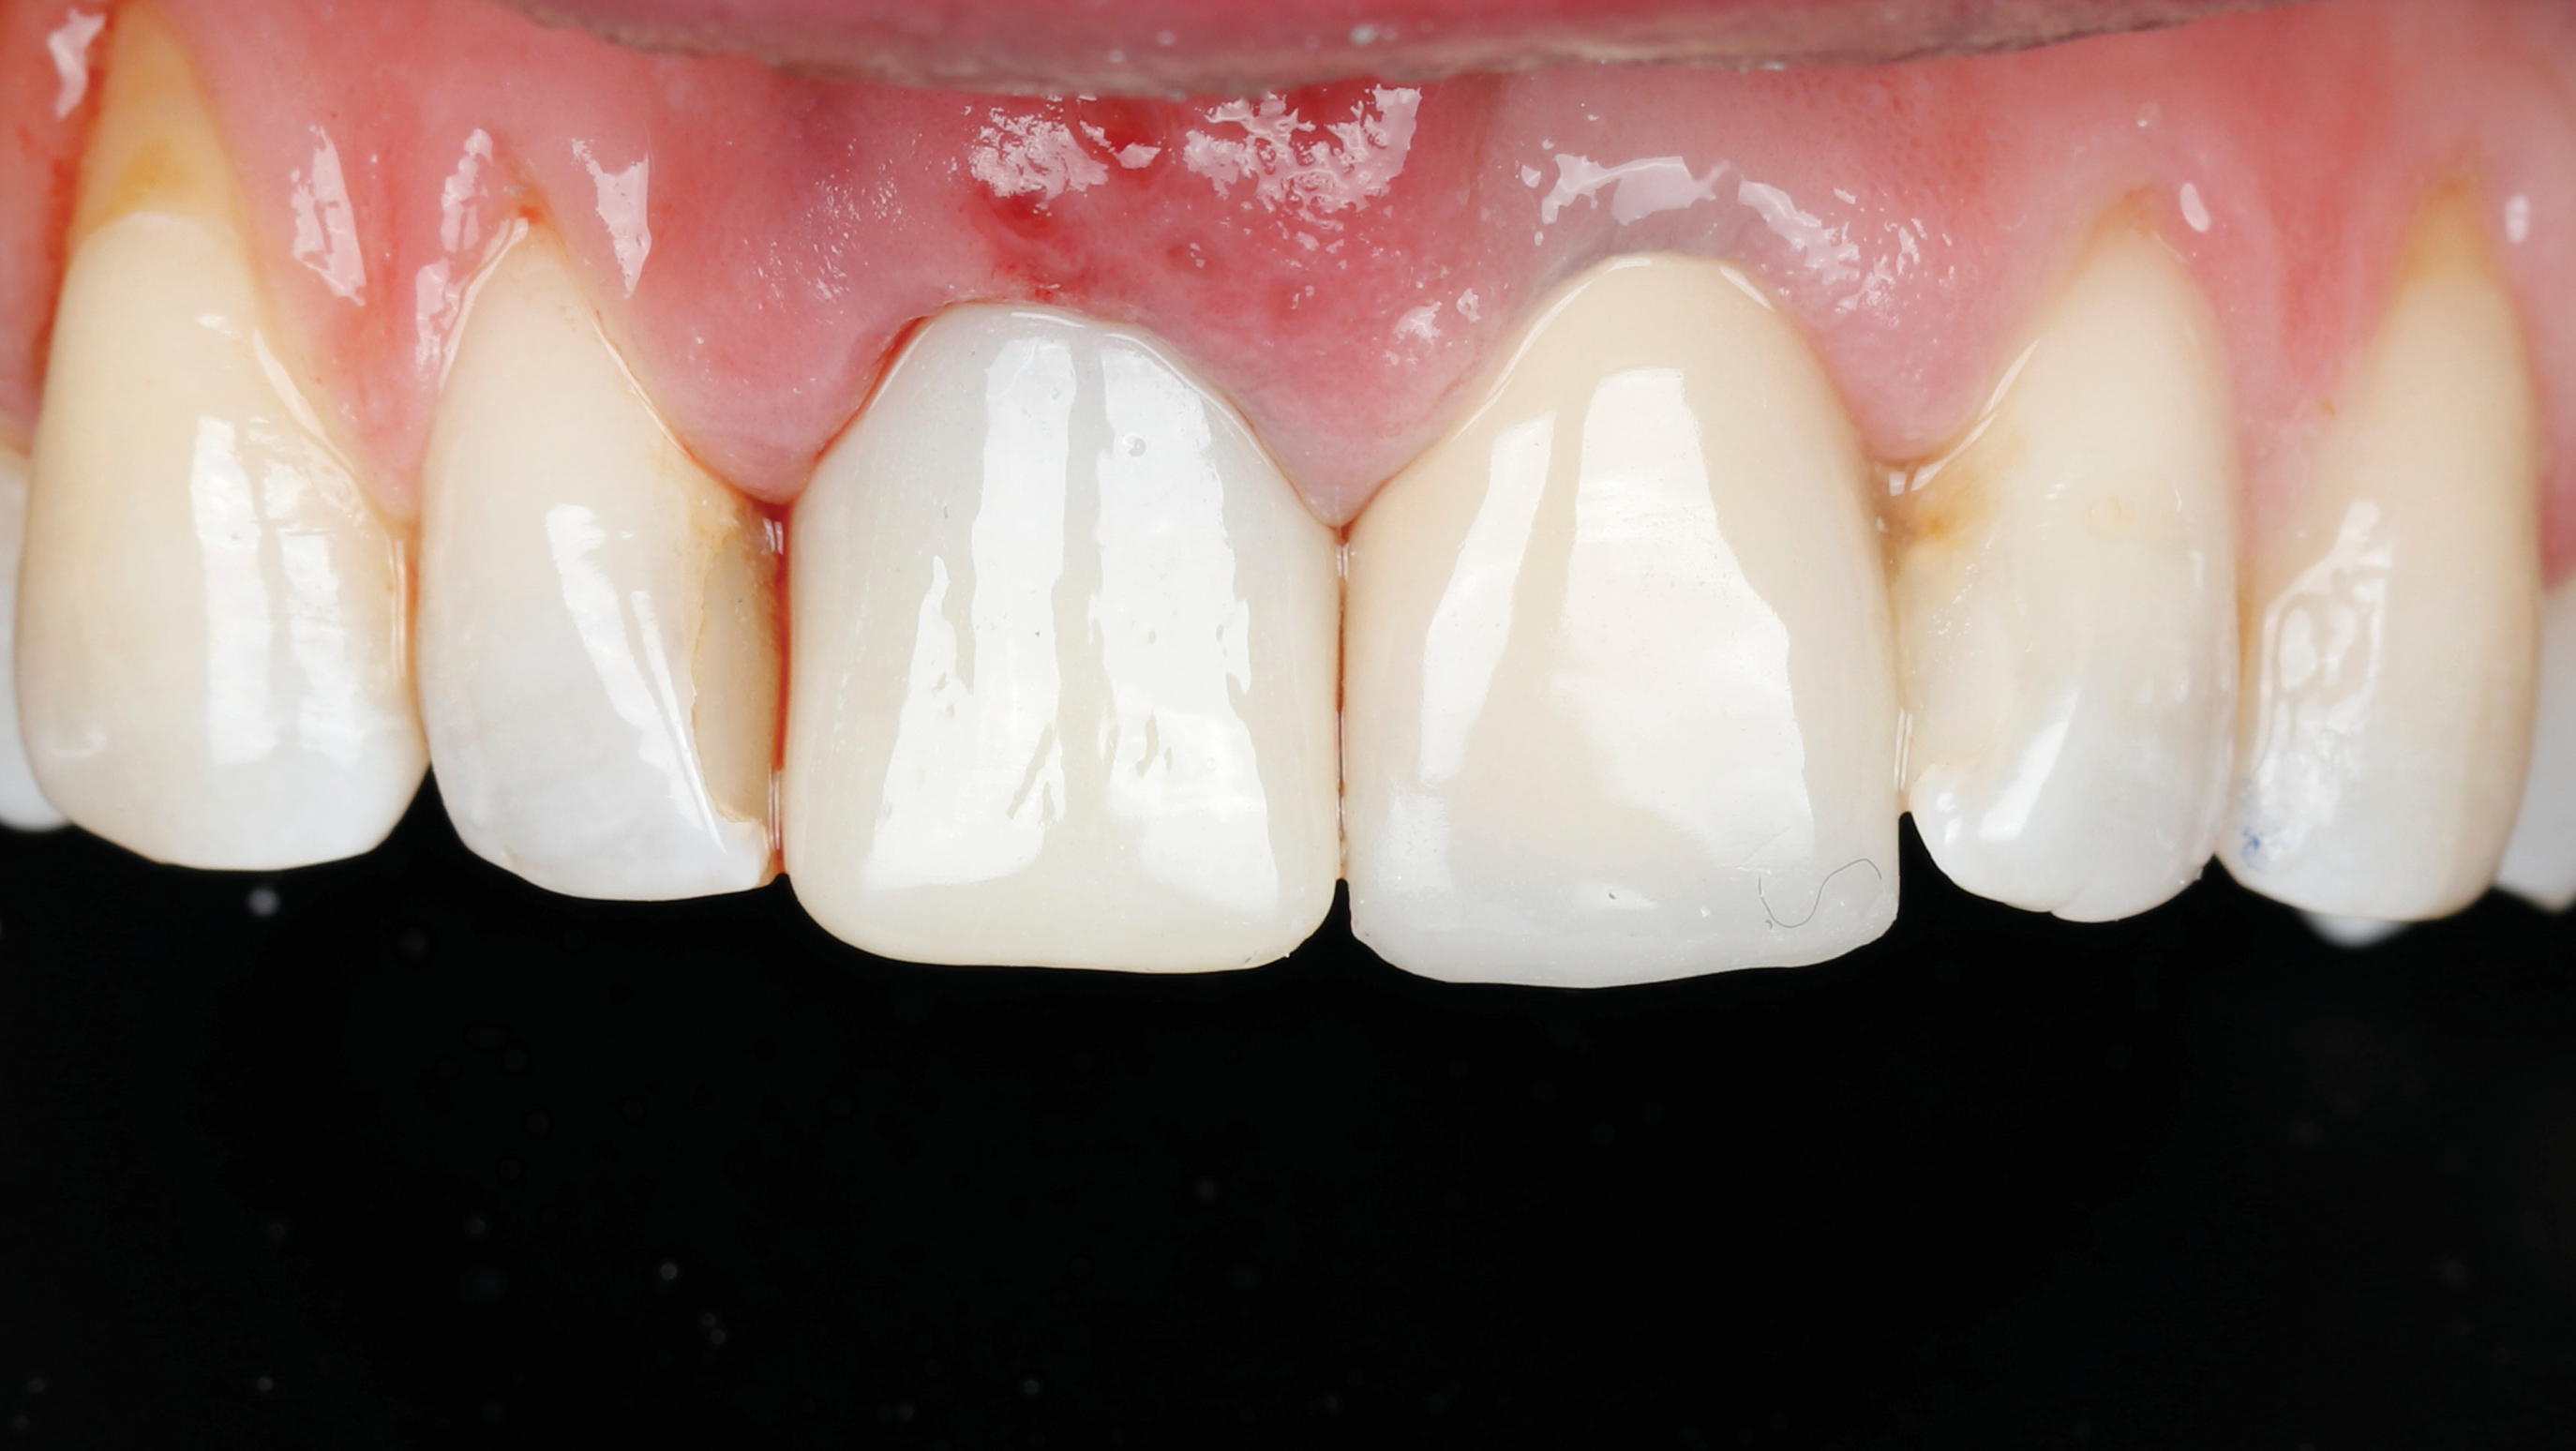

Fig 2. Case presentation of SPOT technique used on central incisor. Initial presentation, facial view, of maxillary right central incisor with hopeless prognosis due to subgingival caries and horizontal fracture.

Figure 2

Fig 20. At 6 months postoperative, the right central incisor site demonstrated significant hard- and soft-tissue volume maintenance. The left central incisor tooth was prepared for a new restoration.

Figure 20

Fig 21. One-year postoperative, final crown restorations. Note soft- and hard-tissue volume maintenance in the right central incisor (socket-shield site).

Figure 21